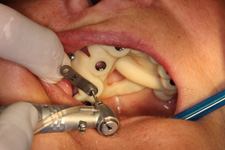

• Řízená implantace - guided surgery – statická navigace

- operace pomocí OP šablon. Ve speciálním programu coDiagnostiX se využívají data z CB CT scanu - tedy údaje o množství a kvalitě kosti, dále data získaná ze scanu modelu čelistí s modelem plánované protetické náhrady (korunky, můstku…)

- tedy údaje tloušťce sliznice, pozice a tvaru náhrady.

Tím máme všechny potřebné údaje pro plánování pozic implantátů, jejich potřebné délce a průměru. Abychom mohli implantáty zavést do naplánovaných pozic v ústech pacienta, umožňuje tento program vymodelovat speciální operační šablonu, která je zhotovena 3D tiskárnou. Pomocí této šablony, která se umístí do úst pacienta, pak probíhá vlastní operace

- zavádění implantátů.